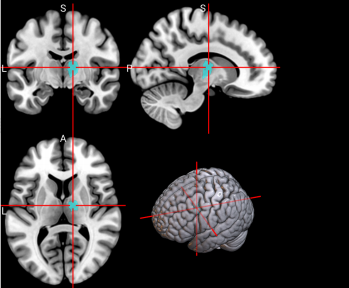

15,

16

L & R Supplementary motor area (SMA)

The SMA plays a role in self-initiated (voluntary) actions and is part of multiple voluntary motor loops [62].

/word/media/image11.png/word/media/image11.png